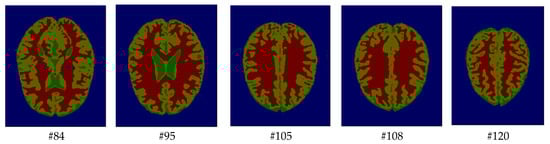

As mentioned before, the images of the first five datasets in Table 3 were used to evaluate the performance of the HMRF-WOA. Figure 1, Figure 2, Figure 3, Figure 4 and Figure 5 show some slices of a T1-weighted image (slices: 84, 95, 105, 108, 120). These brain images correspond to the slices under different types of conditions, such as database type, dimension image, noise level, intensity non-uniformity level, and slice thickness (mm). In Table 1, rows 1 to 5 summarize the parameters of Figure 1, Figure 2, Figure 3, Figure 4 and Figure 5, respectively. Figure 6 represents the ground truth segmentation of slices 84, 95, 105, 108, and 120. In this figure, each column contains the three tissues, GM, WM, and CSF, of each slice. Figure 7, Figure 8, Figure 9, Figure 10 and Figure 11 show the segmentation results, where the four tissues (BG, GM, WM, and CSF) are shown with different colors. The yellow, red, and green colors represent the segmented regions of GM, WM, and CSF, respectively. As we can also see from these figures, the resulting segmented images in Figure 7, Figure 8, Figure 9, Figure 10 and Figure 11 are almost close to the initial images in Figure 1, Figure 2, Figure 3, Figure 4 and Figure 5.

Figure 7. Segmentation results of the slices illustrated in Figure 1.